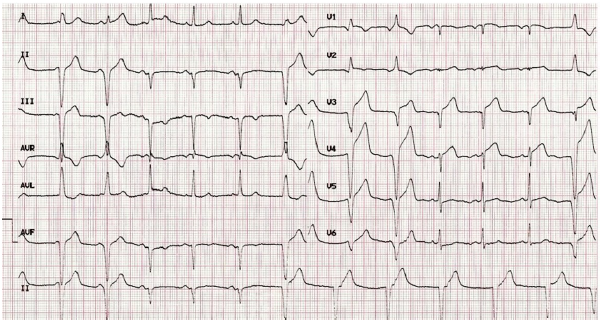

Homem de 77 anos, com histórico de hipertensão sistólica controlada com levanlodipino 2,5 mg, 1x ao dia, apresenta queixa de dispneia aos moderados esforços, há 4 meses, associada a parestesias nos quatro primeiros dedos das mãos há mais de um ano. Realizou os exames laboratoriais mais relevantes para o caso, sem alterações significativas. Ao exame, apresentou: PA 120 x 64 mmHg, FC 84 bpm, ritmo cardíaco regular com presença de B4, sem sopro, murmúrio presente, com estertores crepitantes em bases, ruptura da cabeça longa do bíceps braquial à direita (sinal de Popeye). Realizou o eletrocardiograma reproduzido abaixo.

Pensando na principal hipótese diagnóstica para o caso, seria mais provável encontrar, nesse paciente,